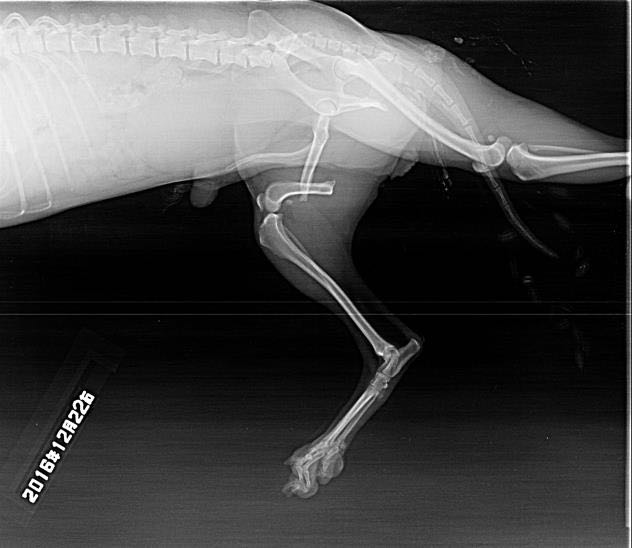

Jack, a beautiful Pomeranian-mix was rescued from the streets of Beijing, China, with a completely displaced fractured of his right femur. This sweet little dog, with such an inquisitive and outgoing nature, desperately needs our help! Jack’s surgery is scheduled for Monday, June 11th. Honestly, we cannot bear to watch him suffer any longer and strongly believe that when you see this amazing little dog, you will gladly contribute what you can to help us reach our goal. We need to raise $2,600 to fund the entire orthopedic surgical procedure necessary to save the leg of this adorable 4-year old dog. With your help, we can work together to change Jack’s life, so that he can finally stand, run and walk, and be pain-free again!

Jack was rescued by Chinese activists nearly 4 years ago, from the streets of Beijing China. When they found him, one eye was gouged out and his right femur was broken into two pieces! Jack was very sick, suffering from pneumonia while living on the streets during the cold winter months in Beijng. But Jack is a spirited young male with a strong will to survive; he recovered in a veterinary clinic over several months. While the Chinese were celebrating the New Year during a month long celebration, Jack was hospitalized and fighting to survive.

Until recently, Jack had been under the care of Chinese activists; however, his fractured femur was never treated. It’s difficult to imagine the pain he has endured for so long! Because of his disability, he was bullied by other dogs because of his handicapped leg and eye. China Doll Animal Rescue 中国娃娃动物救援 (a part of Animal of World Foundation) decided to bring Jack to the United States, the only way he could possibly have a chance of getting the necessary surgery and eventually have a chance to love and be loved in a fur-ever home.

Thank you to the awesome and incredibly generous Jeff Werber, DVM of the Century Veterinary Group, who is donating 100% of his time, x-rays, anesthesia, and use of their operating room and medications. We can only imagine what the cost would have been, if not for Dr Werber’s incredibly generous help for Jack. The fee is for the services of a board certified orthopedic surgeon, who Dr Werber is bringing to his hospital to do the surgery.